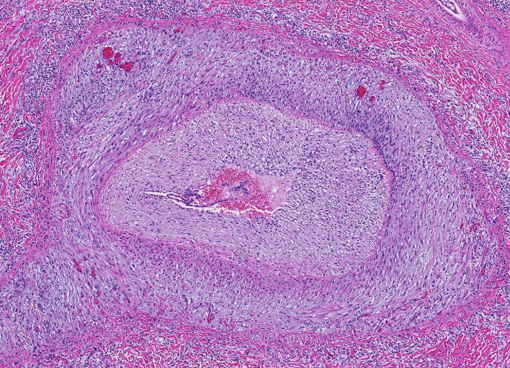

Describe what is being shown here?

Arterial hypertrophy

Marked thickening of the tunica media